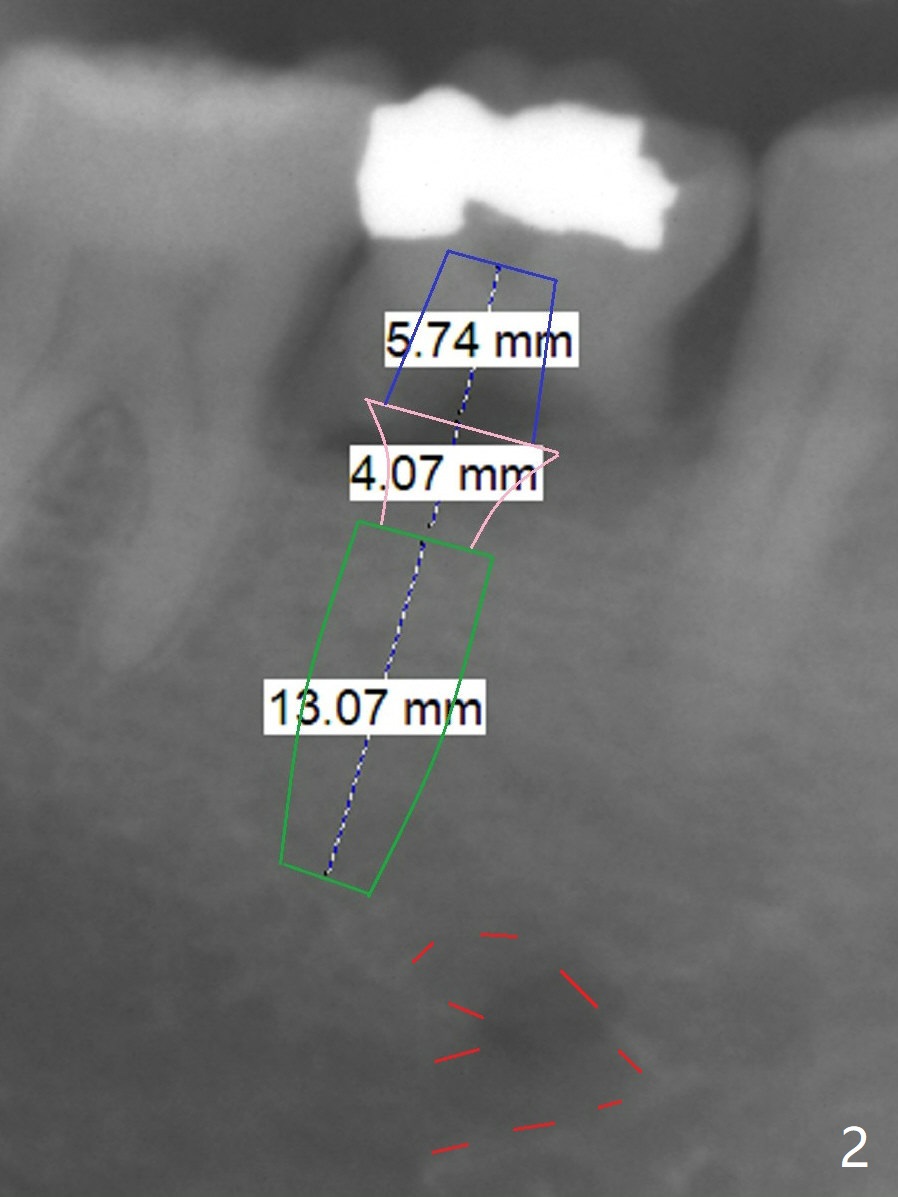

A 51-year-old man has a mobile 2nd primary molar (Fig.1 T).  The latter is much wider than the 2nd premolar.  Since there is crowding in the lower anterior region, it is the best to have limited orthodontic treatment to use the extra space at T to alleviate crowding anteriorly after implant osteointegration.  Although the patient has no intention for orthodontics, an implant will be placed distal (Fig.2 green).  To prevent periimplantitis, make sure that the implant is placed below bone.  Encourage the patient to brush normally over the provisional once there is no pain.  Use Rongeur to remove the septal bone before osteotomy.  Try IS implants if they arrive.